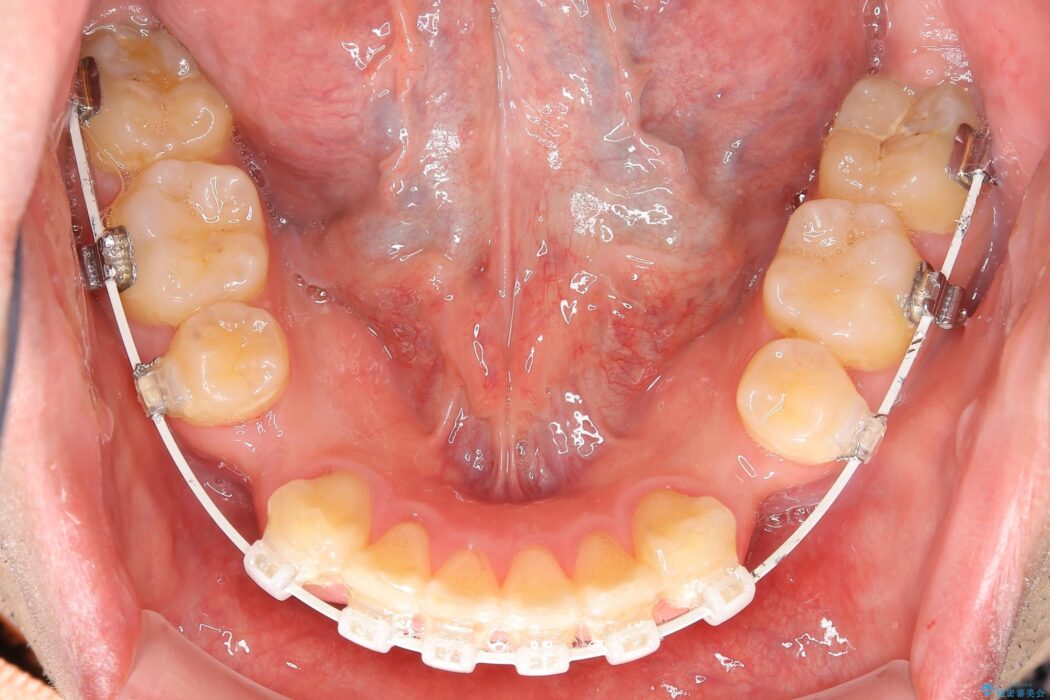

出っ歯とガタつきの改善には抜歯が必要と診断し、上下左右第一小臼歯を抜歯することとしました。

抜歯でスペースができるため、歯の移動量が多いことから表側ワイヤー矯正装置で治療を行いました。